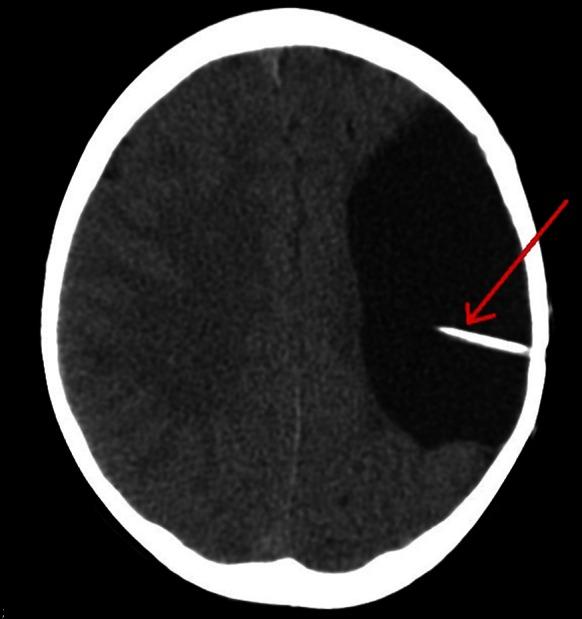

At baseline, abnormalities were found in the right eye: exotropia and lack of foveal fixation. Visual acuity was not achieved. Pupillary responses were normal in both eyes. There was no evidence of nystagmus. Flash visual evoked potentials were normal and equal in both eyes. When repeated one year later the signal had deteriorated in both eyes; the peak times of N2 and P2 had increased. The increased VEP latencies were the only ocular signs noted. After referral to neurosurgery, intracranial hypertension was found and a shunt was performed.

基线时,右眼发现异常:外斜视和中央凹注视缺失。未达到视力。双眼瞳孔反应正常。无眼球震颤证据。双眼闪光视觉诱发电位正常且相等。一年后复查时,双眼信号均变差;N2和P2的峰值时间增加。VEP潜伏期增加是唯一观察到的眼部体征。转诊至神经外科后,发现颅内高压并进行了分流手术。